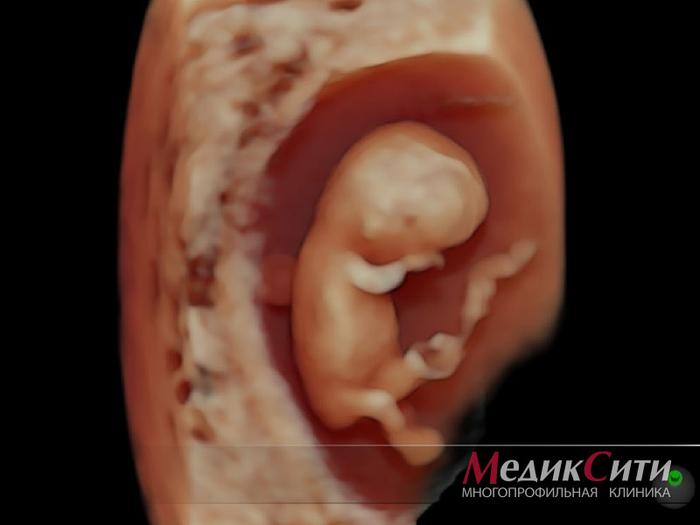

Снимок плода на 11 неделе

Снимок плода на 27 неделе

Снимок плода на 28 неделе

3D УЗИ — это метод, позволяющий получить объемное изображение, благодаря сложному преобразованию двумерной информации в трёхмерную модель. Этот процесс осуществляют с помощью специального трехмерного датчика и программ, входящих в состав аппарата. Образованные объемы можно вращать и рассматривать под разными углами.

4D УЗИ добавляет четвертое измерение — время, что позволяет наблюдать как объемное изображение плода, так и его движения в реальном времени, включая активность и мимику.

УЗИ в 3D и 4D режимах можно проводить на разных сроках беременности, однако качество изображений зависит от положения плода в матке, объема околоплодных вод и наличия препятствий на пути ультразвуковых волн (например, миомы или рубцы на матке могут снижать качество). Если плод расположен ближе к стенке матки, получение качественного трехмерного изображения может быть затруднено.

Важно помнить, что УЗИ в 3D/4D режиме является дополнением к обычному УЗИ и не заменяет его. Измерения размеров плода и исключение пороков развития проводятся с использованием традиционного двухмерного УЗИ.

3D УЗИ плода на 11 неделе и 4 дня

3D УЗИ плода на 21 неделе и 4 дня